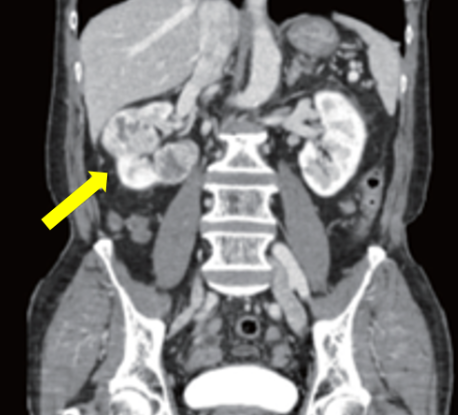

흉부 X선, 단순 복부 촬영, 복부 초음파, 배설성 요로 조영술, 신동맥 조영술, 복부 CT, MRI, 골스캔 등이 사용되며, PET 검사도 일부에서 시행됩니다. 모든 검사를 일괄적으로 시행하기보다는 비침습적·경제적인 순서로 선택합니다. 복부 초음파에서 종양이 발견되면 배설성 요로 조영술은 생략하고 복부 CT로 병기와 특성을 평가합니다.